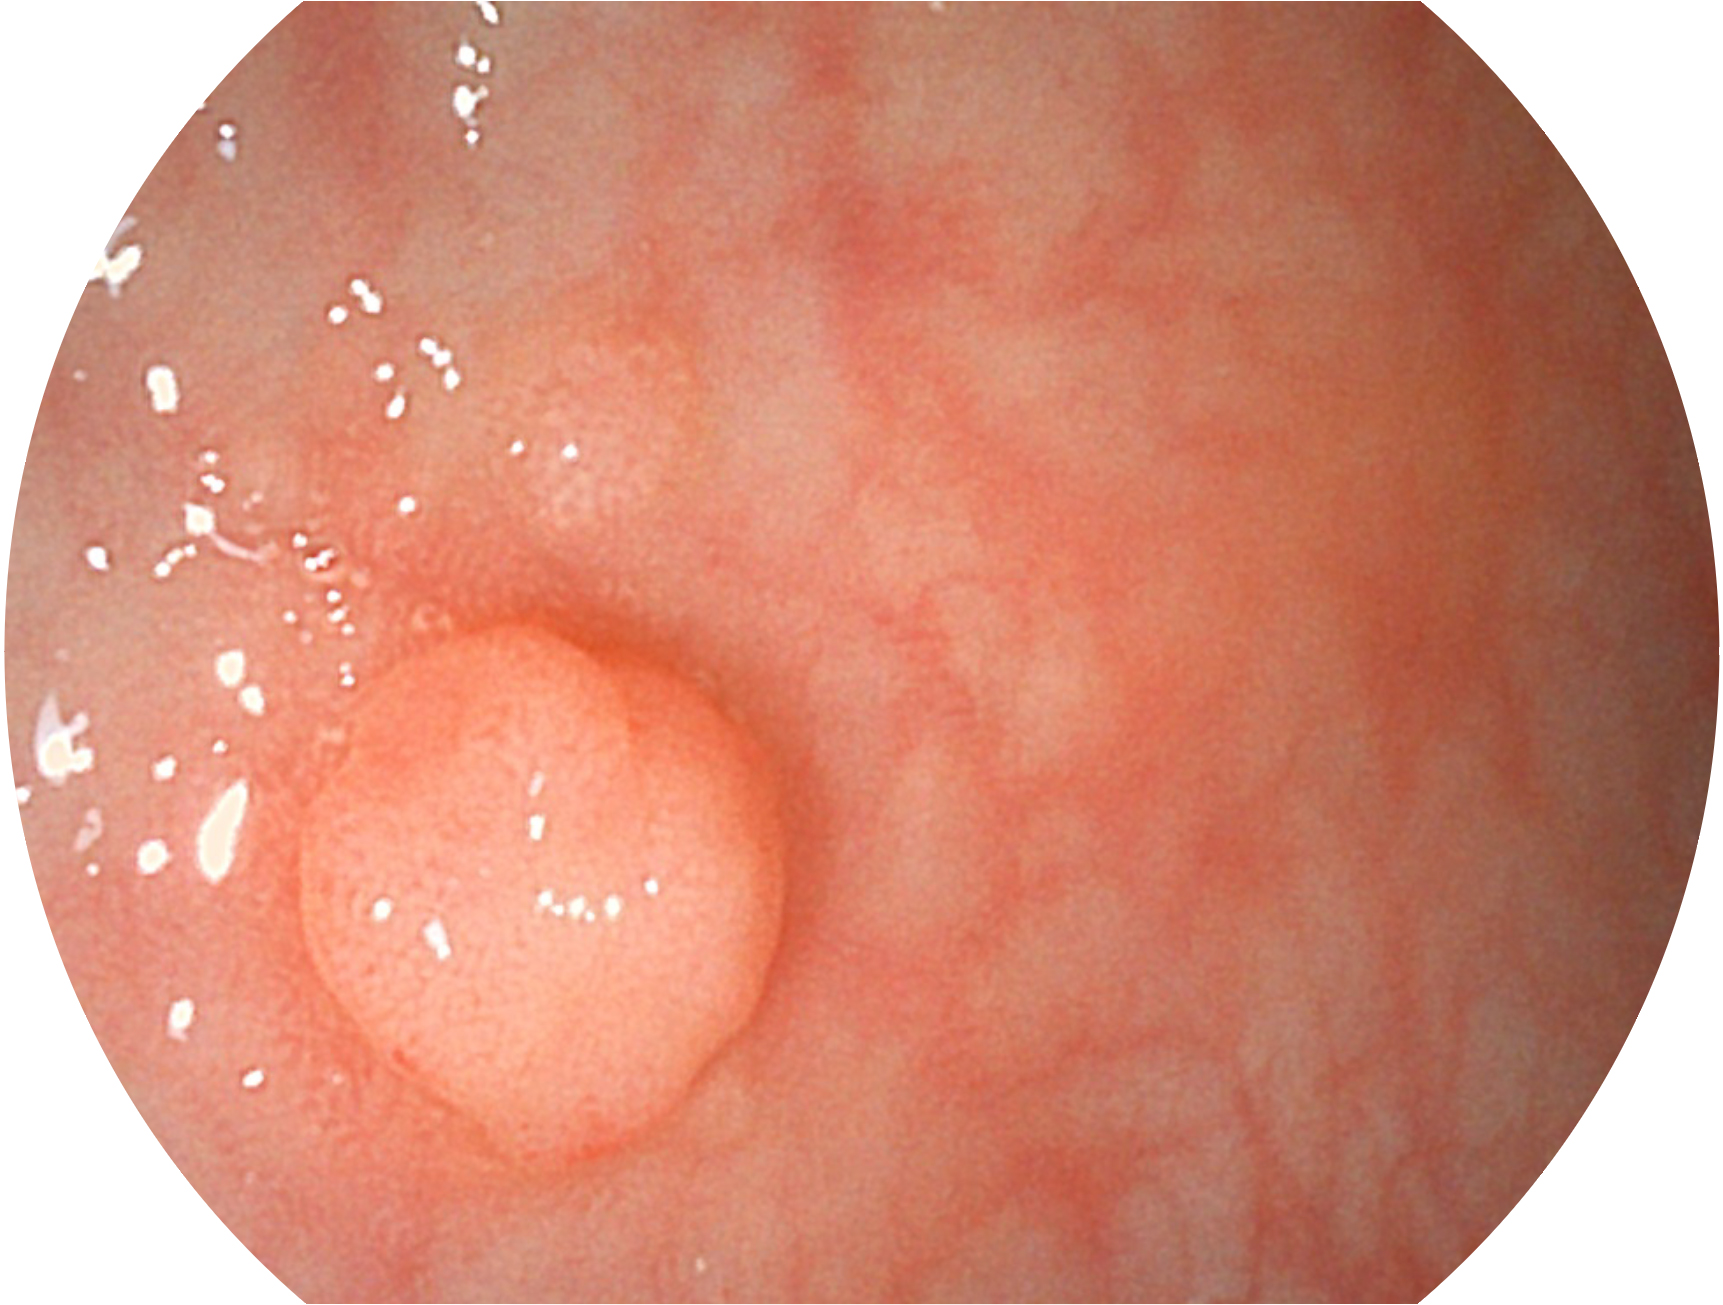

玖鼎集团新开发的内镜染色技术,主要是基于多波长LED 光源的开发,VLS-55Q 四波长LED 光源是由四个不同颜色的LED光按照相应照明模式所规定的特定发光比例进行合束后形成,合束后形成的照明光的光谱由红光、绿光、蓝光及蓝紫光这四个不同的波段范围构成。具有更高光谱自由度,通过光谱比例的控制,实现了聚谱成像技术,英文全称为“Spectral Focused Imaging, SFI”,缩写为“SFI”和光电复合染色成像技术,英文全称为“Versatile Intelligent Staining Technology, VIST”,缩写为“VIST”。